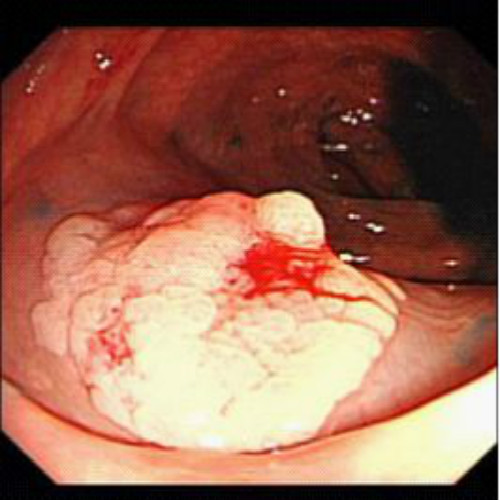

直腸息肉癌

直腸息肉的

直腸息肉